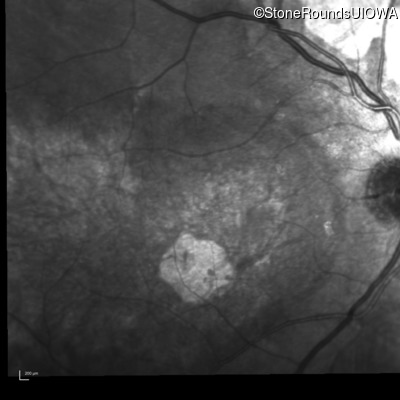

Infrared Fundus Photograph - Right - 20/80

Exemplar

Infrared Fundus Photograph - Left - 20/125